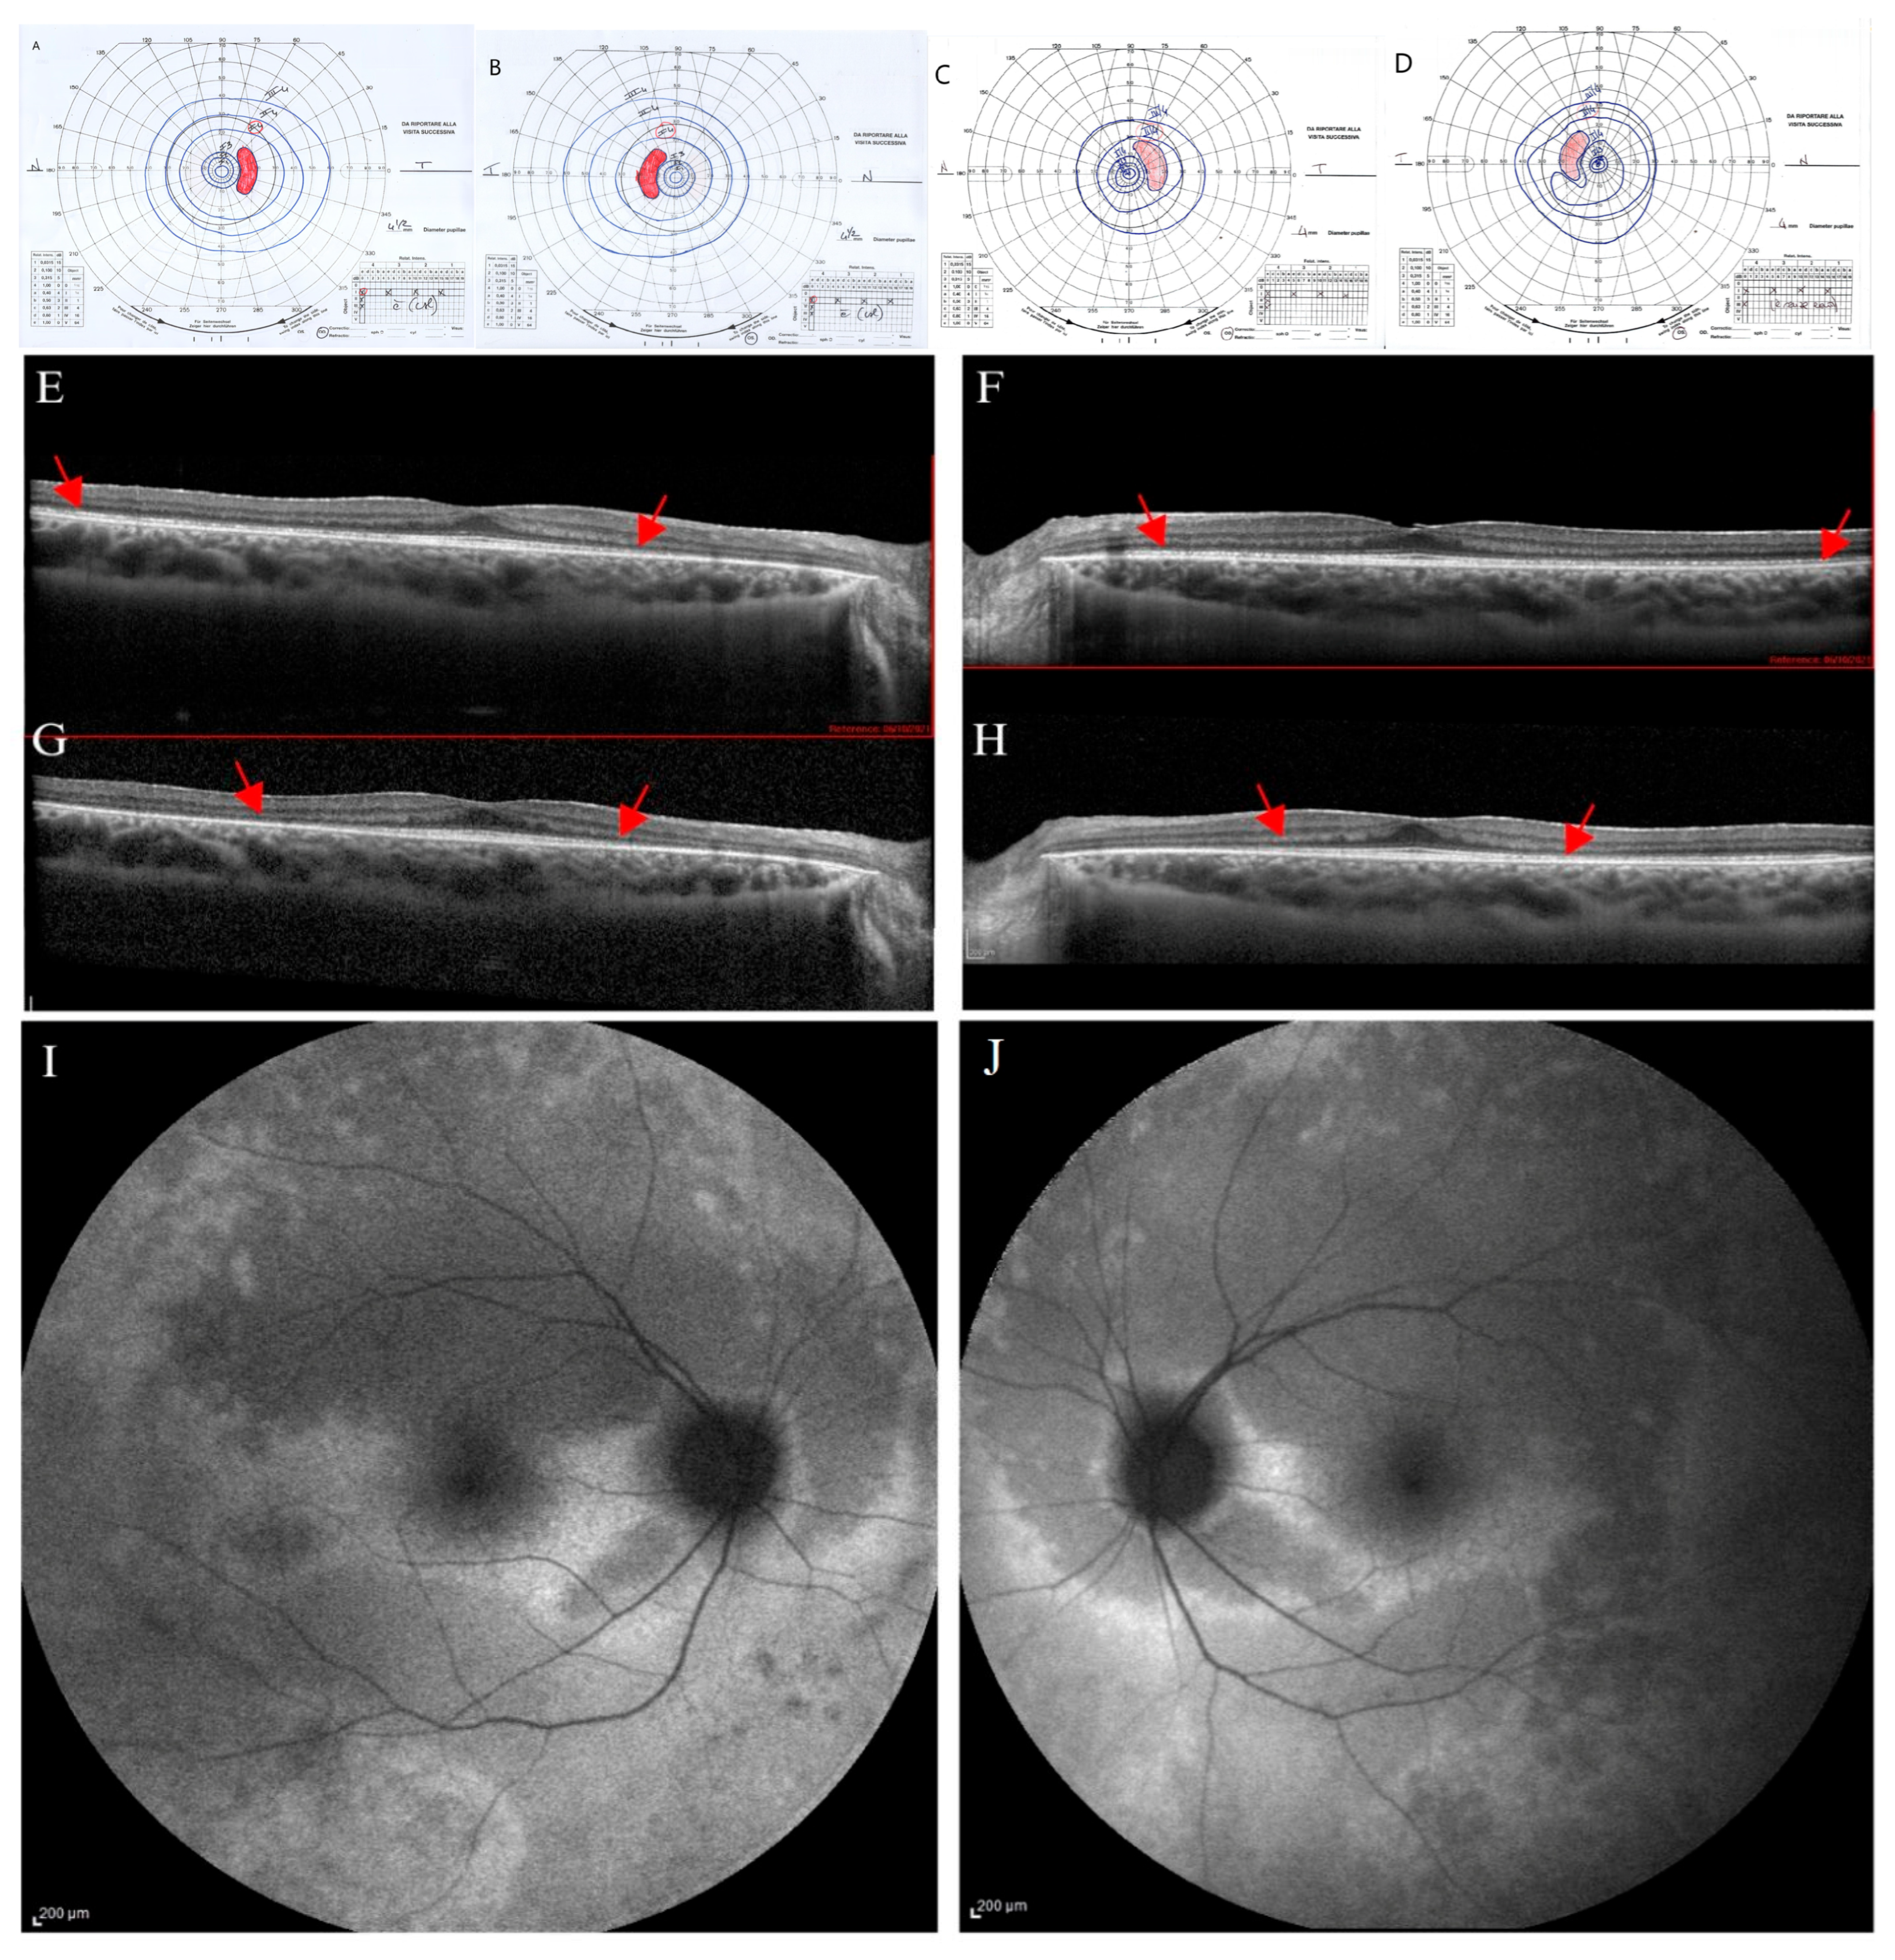

Figure 3. Ophthalmological follow-up (2021–2024) of the younger proband’s sister (II.3). The kinetic visual field (VF) of the right (A) and left eye (B) performed in 2021 show a peripheral narrowing (isopters I/1 to III/4) with sparing of the central area. Progression of the peripheral constriction is shown in the kinetic VF of right (C) and left eye (D) performed in 2024. Spectral-domain optical coherence tomography (SD-OCT) scans of right (E) and left eye (F) performed in 2021 show a focal hyperreflectivity of the internal limiting membrane. Ellipsoid zone (EZ) appears disrupted peripherally and mainly in the nasal parafoveal area (interpapillo-macular region). SD-OCT scans performed in 2024 show a progression of parafoveal EZ disruption in right (G) and left eye (H), as indicated by the red arrows. Fundus autofluorescence (FAF) shows, in right (I) and left eye (J), patchy hyper-autofluorescent areas more evident in the inferior sectors and a hyper-autofluorescent area inferior to the macula only in RE (I).

Dark-adapted and light-adapted full-field ERG showed a reduced b-wave amplitude, and mfERG recordings showed reduced function from the foveal center up to the 10 degrees of foveal eccentricity, depicting a progressive bilateral cone-rod dystrophy. SD-OCT scans showed in OU a preserved retinal profile with a normal foveal shape (Figure 3E,F). Inner and outer retinal layers were preserved overall in terms of reflectivity and morphology in the foveal region. EZ appeared disrupted peripherally and mainly in the nasal parafoveal area (interpapillo-macular region). In OU, FAF showed patchy hyper-autofluorescent areas more evident in the inferior sectors and a hyper-autofluorescent area inferior to the macula only in RE (Figure 3I,J).

Over the years (2024), the patient reported the onset of photophobia, along with a stationary BCVA, chromatic test results, and mfERG; progression of the visual field constriction (Figure 3C,D) and SD-OCT EZ parafoveal disruption was observed (Figure 3G,H).